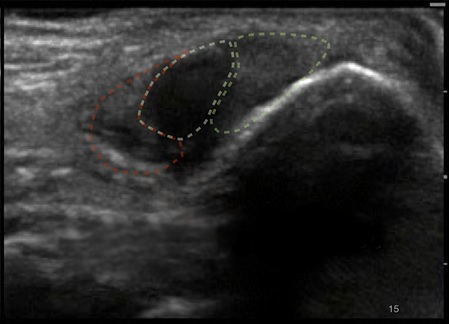

Bild: Fuß und Sprunggelenk, Peronealsehnen mit Anisotropien